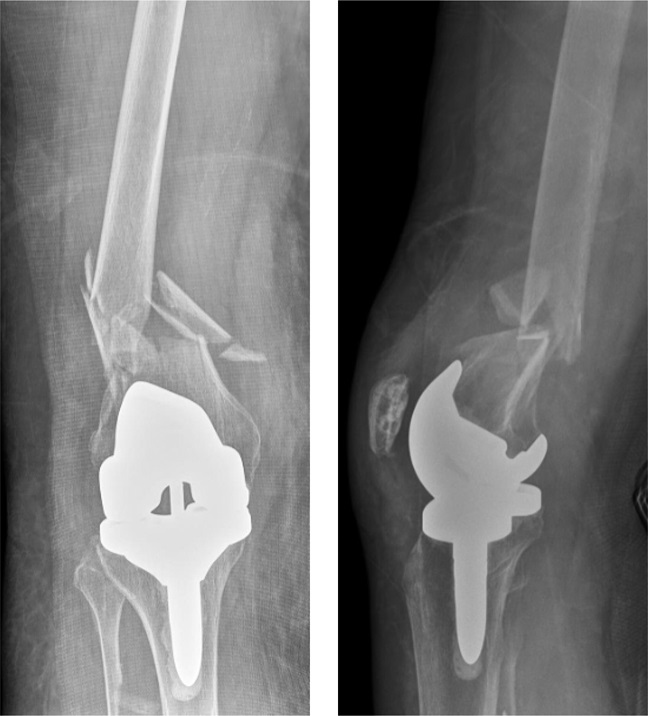

X-ray showing a comminuted periprosthetic femur fracture above the total knee replacement.

Reproduced from Van Rysselberghe NL, Campbell S, Goodnough LH, Amanatullah D, Gardner, M, Bishop J: To Fix or Revise: Differences in Periprosthetic Distal Femur Fracture Management Between Trauma and Arthroplasty Surgeons. J Am Acad Orthop Surg 2022; 30[1]:e17-24.